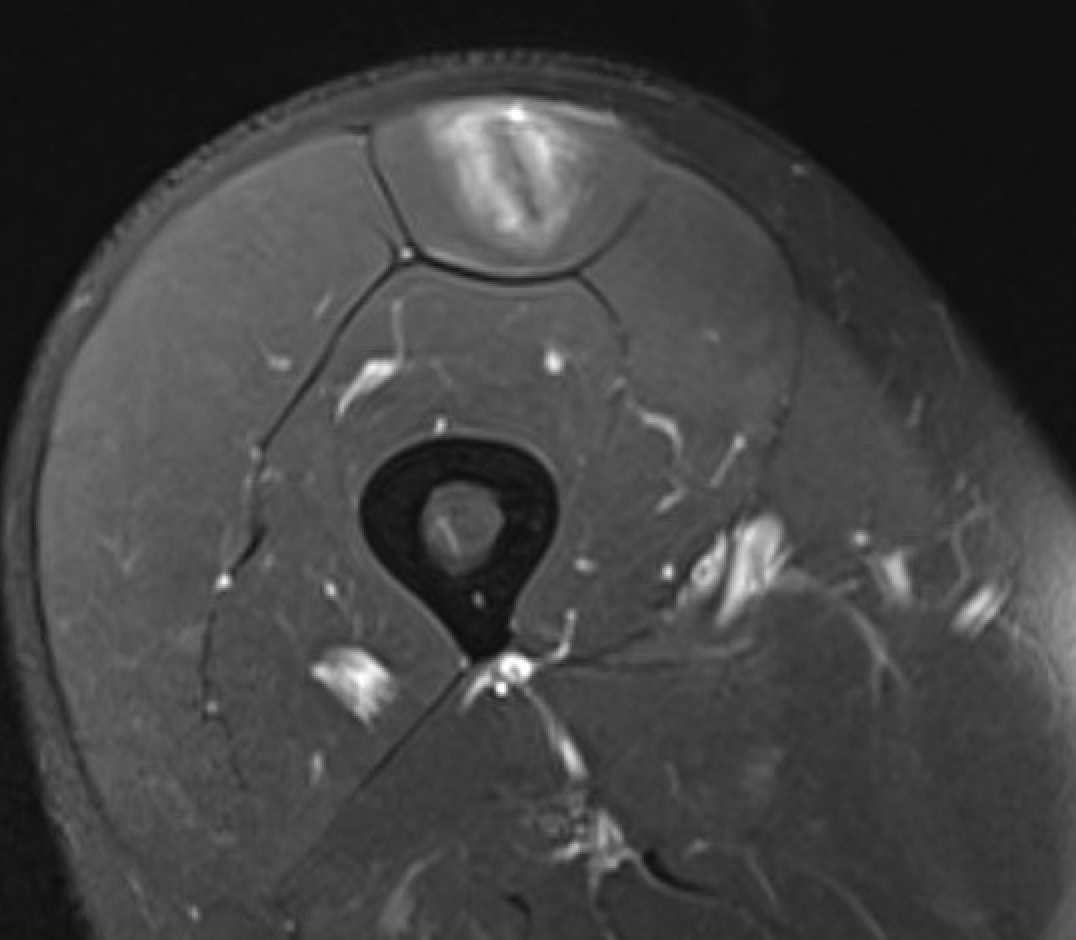

Normal central tendon

Proximal myotendinous / tendon injuries

MRI